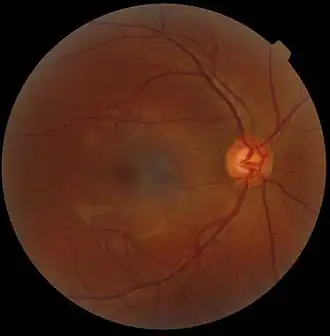

In microscopy, an artifact is an apparent structural detail that is caused by the processing of the specimen and is thus not a legitimate feature of the specimen. In light microscopy, artifacts may be produced by air bubbles trapped under the slide's cover slip.[1]

A crush artifact is an artificial elongation and distortion seen in histopathology and cytopathology studies, presumably because of iatrogenic compression of tissues. Distortion can be caused by the slightest compression of tissue and can provide difficulties in diagnosis.[2][3] It may cause chromatin to be squeezed out of nuclei.[4] Inflammatory and tumor cells are most susceptible to crush artifacts.[4]